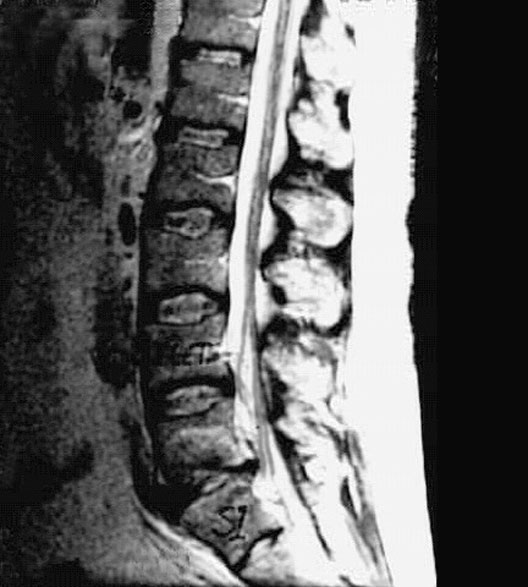

Lumbar Spine Zoom

1. Nucleus pulposus

2. Anulus fibrosus

3. Rootlets of cauda equina